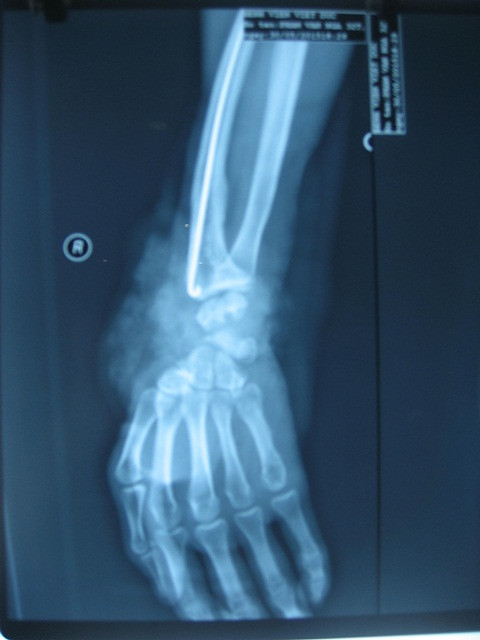

Chụp X quang sau mổ